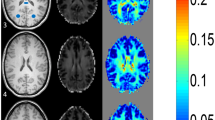

To study the MT phenomenon, a three-dimensional (3D) gradient echo sequence (TR/TE 32/8, flip angle 6°) was performed, and 4-mm/2-mm overlapping sections were concurrently obtained both with and without the application of MT binomial prepulse applied on-resonance. Images of this sequence obtained before application of MT prepulse had proton-density contrast due to the short TE and small flip angle (Fig. 1a). The MT sequence performed in the axial plane (perpendicular to the intercommisural line, i.e., the anterior commissure to posterior commissure line, or AC-PC line) was part of our standard protocol. Images obtained after application of the MT prepulse depict structures of high MTR with low signal intensity and those of low MTR with higher intensity (Fig. 1b). The duration of a complete MR examination ranged from 15 to 25 min. MTRs were calculated from circular regions of interest (ROIs), with a minimum size of 0.5 mm2. In all cases, UBOs observed on T2-weighted images were also detectable in proton density images of the MT sequence; therefore, ROIs were positioned at an image without MT and copy–pasted to the corresponding image with MT. Signal intensity measurements were performed bilaterally in the following regions: cortex and WM of the frontal and occipital lobe, caudate nucleus, putamen, globus pallidus, thalamus, optic chiasm, internal capsule, genu and splenium of the CC, hippocampus, cerebral peduncles, and cerebellar WM. Care was taken to avoid the partial volume effect of CSF when defining ROIs. MTR was calculated as: (SI0-SIm)/SI0×100% where SI0 is the signal intensity from the image acquired without a MT pre-pulse and SIm refers to signal intensity from an image acquired with MT prepulse.

UBOs in T2-weighted images lacking mass effect and enhancement after contrast infusion, compatible with “hamartomas,” were observed in the globus pallidus (6/7 patients), cerebral peduncles (3/7), periventricular WM (2/7), internal capsule (2/7), cerebellar WM (2/7), and hippocampus (1/7). Optic chiasm glioma appearing hyperintense in T2-weighted images and heterogeneously enhancing after contrast administration was observed in one patient. There was no significant difference in MTR values of normal-appearing GM and WM structures between patients and controls (Table 1). MTR of optic chiasm glioma (56.6) was lower compared with MTR of normal WM in controls (63.6±1.7). MTR values of UBOs in the different anatomic locations were significantly lower compared with MTRs of the corresponding normal-appearing anatomic regions in patients and controls (Table 1). The area of CC, WMV, GMV, and IBT were significantly larger in patients compared with controls (Table 2). There was no significant difference in CSFV between patients and controls (Table 2).